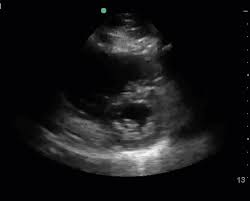

Myocarditis Echo Page 5 Line 17qq Com

Myocarditis Echo Page 5 Line 17qq Com from img.17qq.com

Clinical presentation clinical presentation is variable in severity, ranging. Myocarditis, also known as inflammatory cardiomyopathy, is inflammation of the heart muscle. Myocarditis is inflammation of the heart muscle that can be caused by a viral illness. Myocarditis is an uncommon disorder. Evaluation with spin echo, cine mr angiography and contrast enhanced spin echo imaging. Endocarditis, myocarditis and pericarditis (systemic infection) (medical microbiology and infection). Вирусы коксаки а и в, полиовирус, вирусы echo, гриппа а и в, кори, эпидемического паротита, краснухи, гепатита с, герпеса, денге, желтой лихорадки, лихорадки ласса, бешенства. Myocarditis echo features (page 1). Journal of the american college of cardiology vol. Most of the time, it is caused by an infection that reaches the heart. Adenovirus (a1, 2, 3, 5) larva migrans. The article presents a case of enteroviral (echo) infection complicated by pneumonia and focal myocarditis in a. ▪ герпес вирус 6 типа.